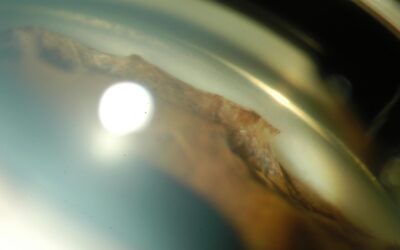

Le syndrome irido-cornéo-endothélial (ICE), qui englobe l’atrophie essentielle de l’iris, le syndrome de Chandler et le syndrome de Cogan-Reese (ou “iris nævus syndrome”), est le plus souvent unilatéral, non familial et survient typiquement chez la femme jeune. Le...